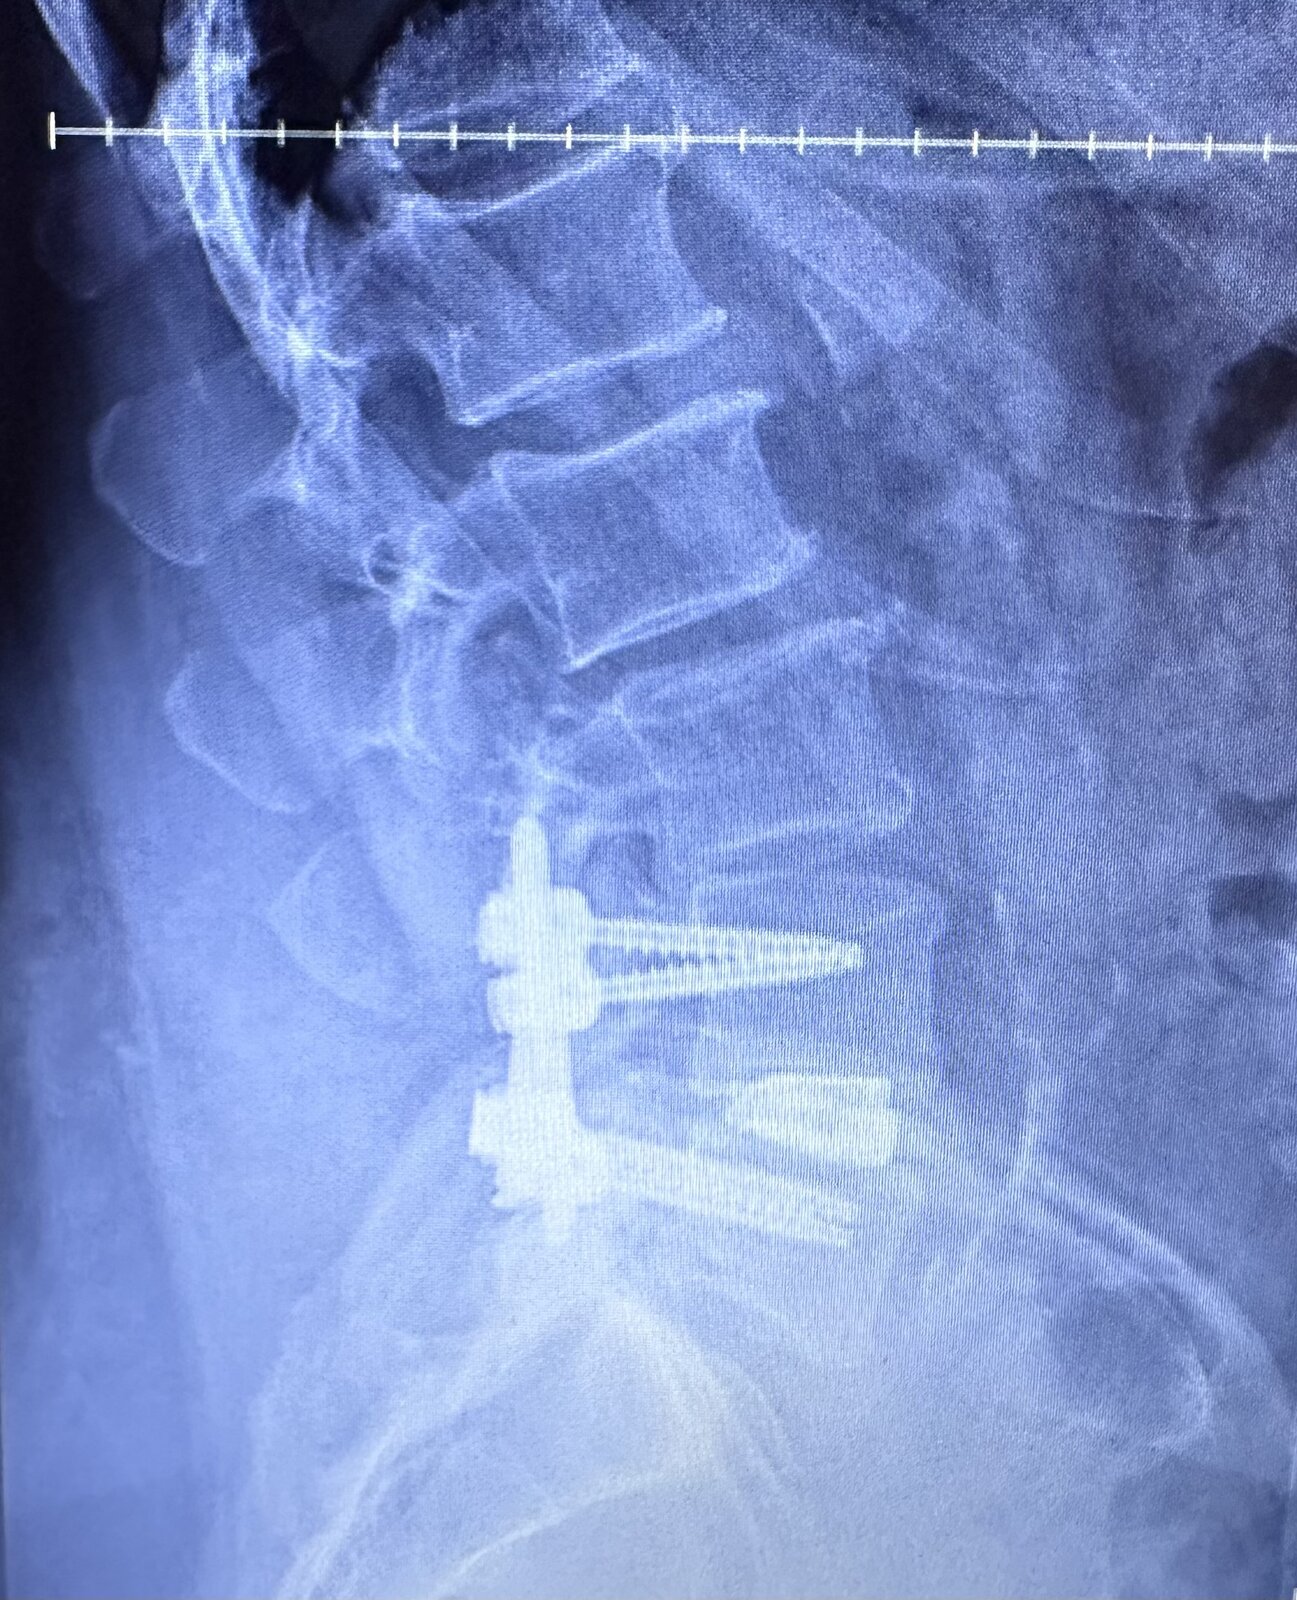

Tell me about it. Six weeks post op.

spine.jpg

For what it's worth, this is an MRI of my neck from 2017, I'm sure it has not improved since then. The main reason I have not gone with a Trend "helmet" is because I am concerned about the weight of the battery on my head, putting extra strain on the neck.